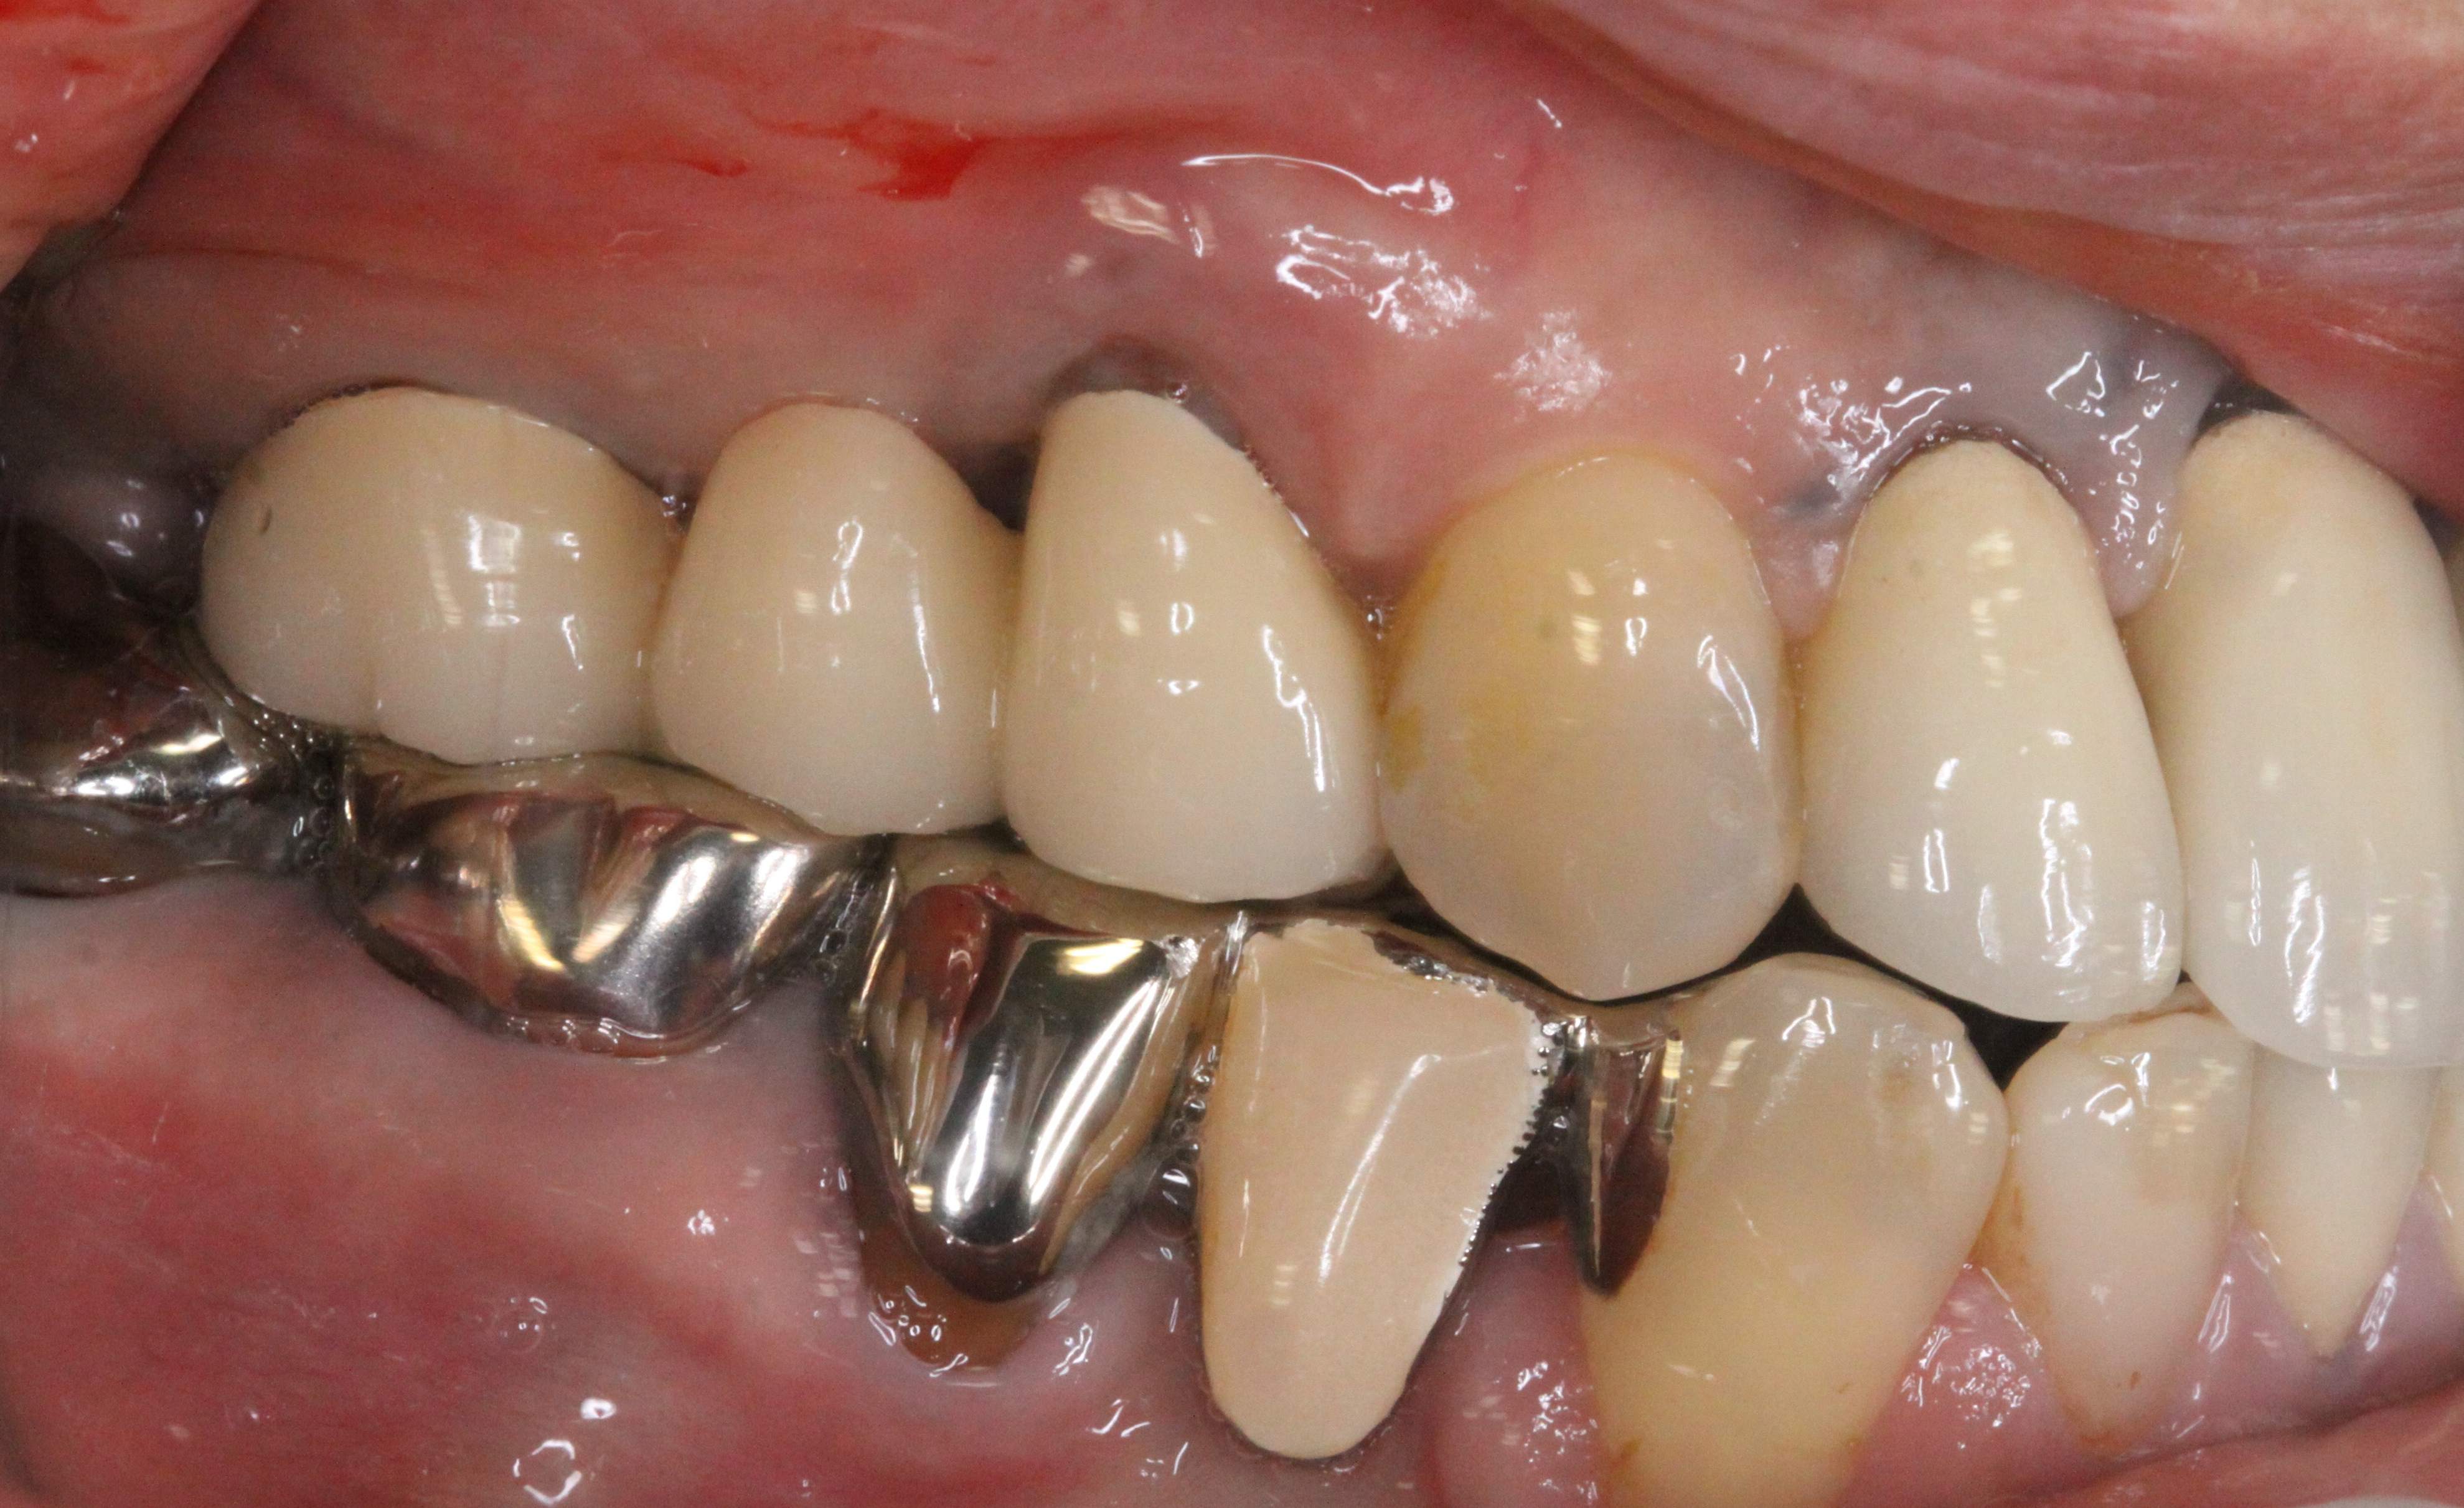

治療途中

左のX線の矢印で示してある歯が割れていたので、一旦歯を抜いてきれいにしました。